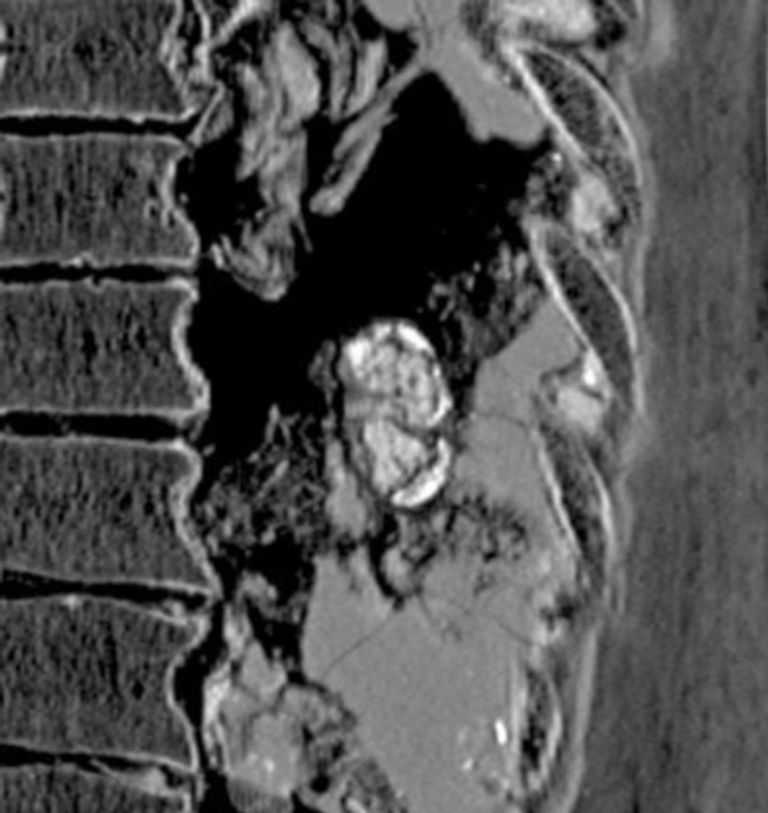

وخلال دراسة نشرت في "المجلة الدولية لعلم الأمراض القديمة"، أظهر التصوير المقطعي المحوسب، أن المومياء " إرتييرو" الموضوعة في الكارتوناج، والتي تعود إلى الفترة الانتقالية الثالثة (من 1070 قبل الميلاد حتى 664 قبل الميلاد)، كان لديها بنية صغيرة كثيفة على شكل حبة الفول في المنطقة اليسرى أسفل الظهر، ويدعم هذا الموقع التشريحي والتحليل المورفولوجي والهيكلي تشخيص مرض السل الكلوي في مرحلته المتأخرة.

ويقول الفريق البحثي، إنه إذا كان هذا التشخيص صحيحًا، سيكون هذا أقدم مثال على مرض السل الكلوي، وأول مثال يتم تسجيله في مومياء مصري قديم تم تحنيطه عمدًا.